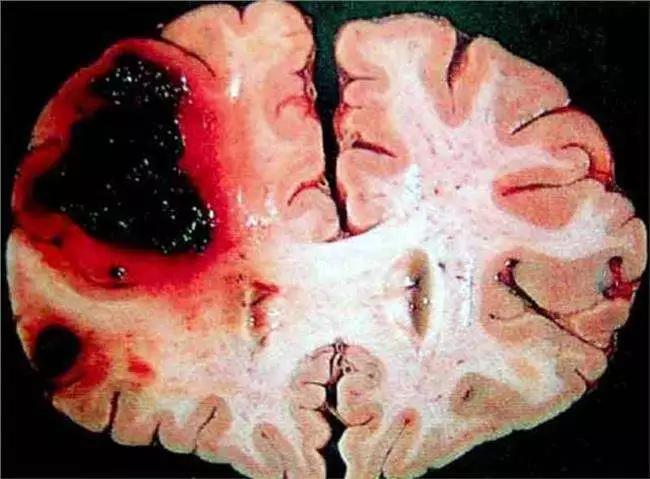

腦溢血就是平時所說的腦出血,是神經(jīng)外科的常見危重急癥。腦出血能恢復到什么程度,或者腦出血的預后怎么樣,取決于出血的總量以及出血的部位。

如果出血量比較大,在50ml以上,而且是在大腦的功能區(qū),預后比較差,甚至有生命危險。如果腦出血的量比較小,只是少量出血,而且在大腦的非功能區(qū)域,通過大腦的自身的血液的吸收,以及藥物的治療,可以治愈。

還有比較特殊的情況,或者比較兇險的情況,就是腦干出血、腦室出血,該部位的出血死亡率非常高,通常在度過危險期以后,即使存活下來,致殘率也非常高,嚴重影響患者的自理能力以及社會功能。